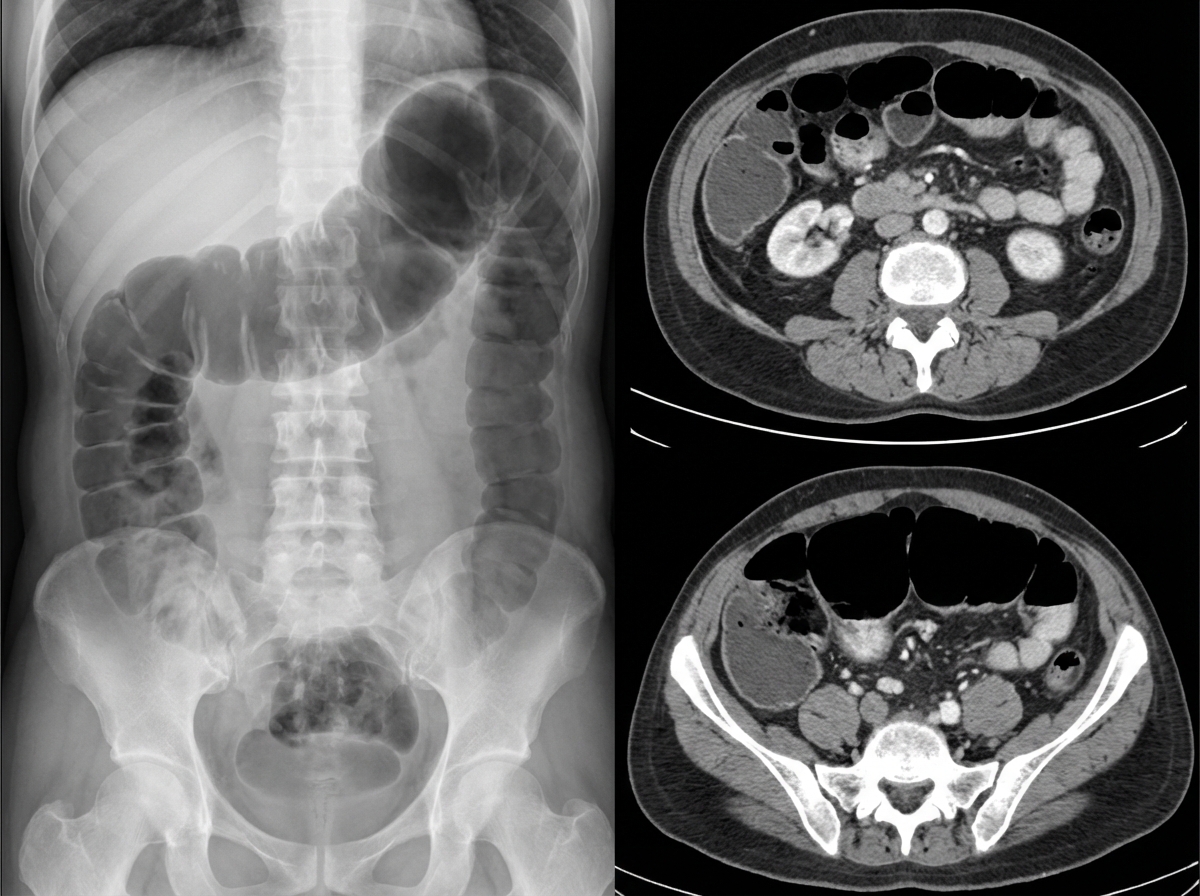

A 76-year-old female is brought to the emergency department after being found unresponsive in her room at her nursing facility. Past medical history is significant for Alzheimer's disease, hypertension, and diabetes. Surgical history is notable for an open cholecystectomy at age 38 and multiple cesarean sections. On arrival, she is non-responsive but breathing by herself, and her vital signs are T 102.9 F, HR 123 bpm, BP 95/64, RR 26/min, and SaO2 97% on 6L nasal cannula. On physical exam the patient has marked abdominal distension and is tympanic to percussion. Laboratory studies are notable for a lactic acidosis. An upright abdominal radiograph and CT abdomen/pelvis with contrast are shown in Figures A and B respectively. She is started on IV fluids and a nasogastric tube is placed to suction which returns green bilious fluid. Repeat vitals 1 hour later are T 101F, HR 140 bpm, BP 75/44, RR 30/min, and SaO2 is 100% on the ventilator after she is intubated for airway concerns. What is the next best step in management?